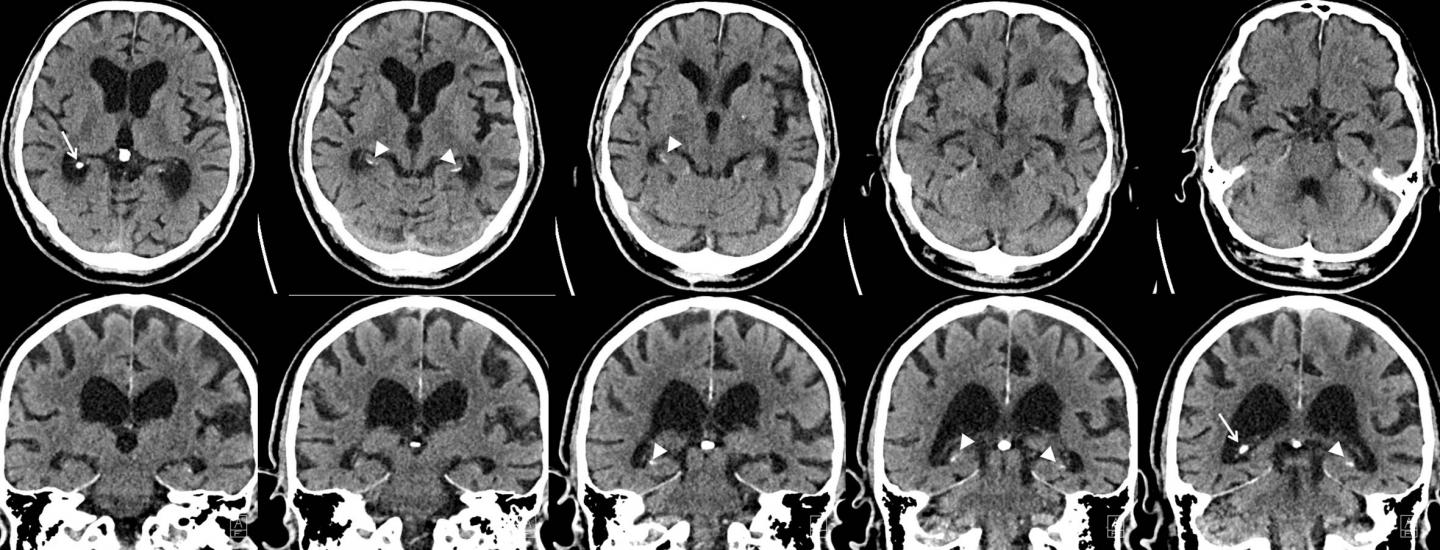

Advances in imaging have provided opportunities to explore the role of hippocampal calcifications in dementia. The development of multiplanar brain CT scans has enabled better distinction between hippocampal calcifications and calcifications in nearby brain structures like the choroid plexus.

"A multiplanar CT scan makes it possible to see the hippocampus in different anatomical planes; for example, from top to bottom, right to left and front to back," Dr. de Brouwer said. "Before multiplanar CT scans, hippocampal calcifications were often mistaken for choroid plexus calcifications. So with multiplanar CT scans, hippocampal calcifications are better distinguished from calcifications in other areas."